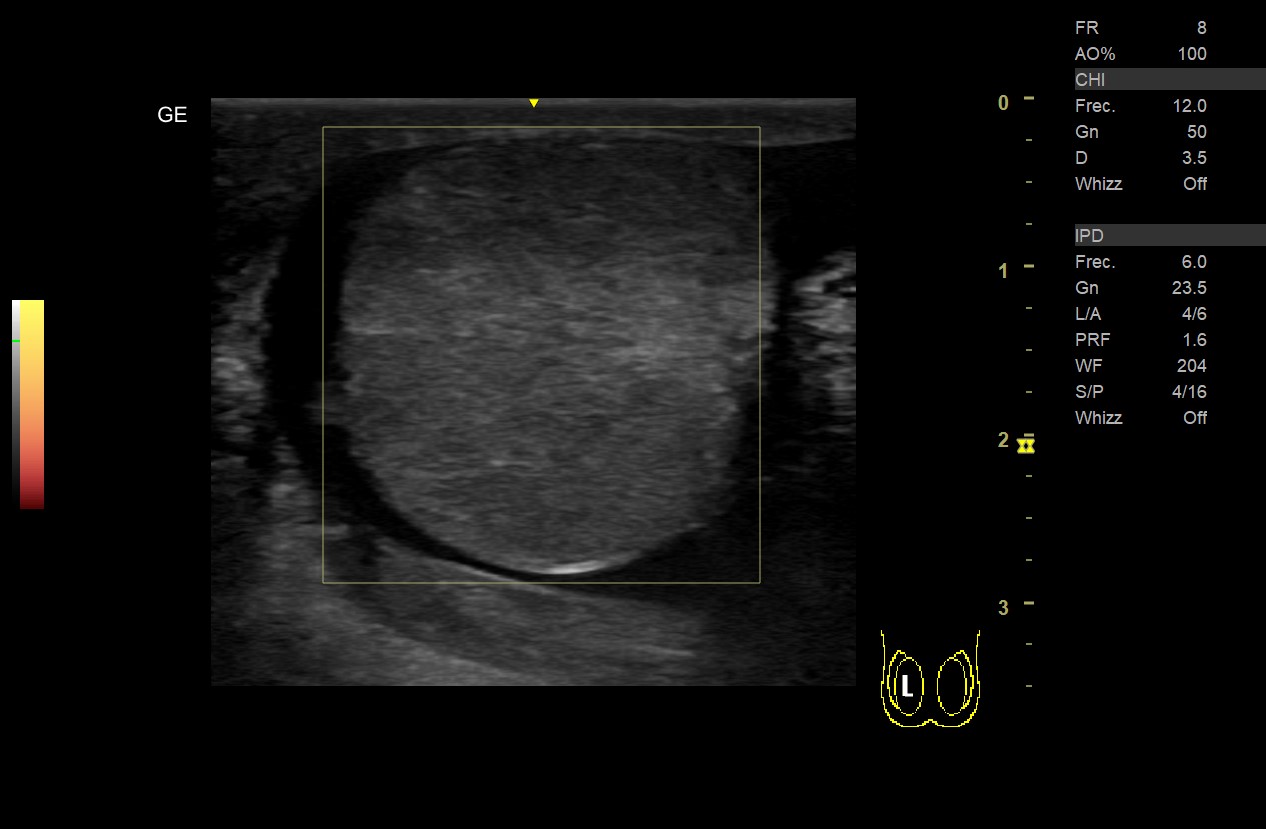

Ecografía testicular:

• Teste derecho: aumento de volumen con ecogenicidad heterogénea (áreas más hipoecogenicas), sin captación Doppler color ni power en teste o epidídimo derecho y presencia de líquido en bolsa escrotal.